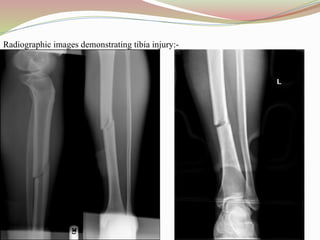

Radiographic images demonstrating tibia injury:-

2. TIBIA INJURY: Is a break of the tibia (shin bone).

 CAUSES: Tibia injury can be caused by:-

 Traumatic injuries, such as motor vehicle accidents or falls

 Repetitive stress on the shinbone and the connective tissues that attach your muscles to the bone

like in Sports that involve repeated impact to the shinbones, such as long-distance running

 Injuries from contact sports such as football or hockey.

 Osteoporosis, which makes the bones weaker than usual.